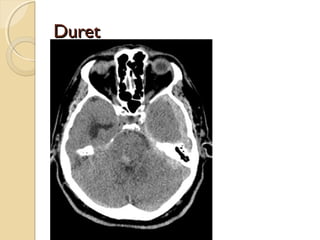

BRAINSTEM INJURYBRAINSTEM INJURY

By direct or indirect forces

Most commonly associated with DAI

Involves the dorsolateral midbrain and upper

pons and is usually hemorrhagic

Duret hemorrhage is an example of indirect

damage: tearing of the pontine perforators

leading to hemorrhage in the setting

transtentorial herniation

<20% of brainstem lesions are seen on CT

BRAINSTEM INJURYBRAINSTEM INJURY Bydirect or indirect forces Most commonly associated with DAI Involves the dorsolateral midbrain and upper pons and is usually hemorrhagic Duret hemorrhage is an example of indirect damage: tearing of the pontine perforators leading to hemorrhage in the setting transtentorial herniation <20% of brainstem lesions are seen on CT